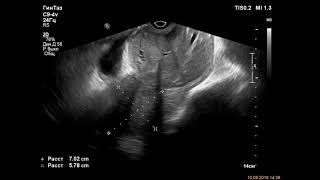

В Санкт-Петербурге скончался онколог Андрей Павленко, который с марта года боролся с выявленным у него раком желудка. О смерти медика в Facebook написала его супруга Анна , которая поддерживала его весь период борьбы с болезнью. В начале года Павленко выложил в соцсети пост, в котором сообщил, что болезнь оказалась сильнее, и у него больше не осталось шансов на выздоровление. В посте медик попросил не оставлять после его смерти жену и двоих детей, а также обратился к таким же пациентам, которые в данный момент борются с раком. Он попросил их не опускать руки и отметил, что шанс на выздоровление есть у каждого. В году Павленко ощутил первые симптомы опухоли, которая к тому моменту уже перешла в третью стадию и дала метастазы. По словам онколога, он ощутил боли в области живота, но списал их на гастрит или язву, однако решил пройти обследование.

Эти страшные слова говорит петербургский хирург-онколог Андрей Павленко, два года боровшийся с раком желудка. Андрей Павленко умер сегодня в Санкт-Петербурге. Вторая половина пойдет моей семье. Напомним, что хирург-онколог Клиники высоких медицинских технологий имени Н. Пирогова в Санкт-Петербурге Андрей Павленко узнал о том, что у него рак желудка третьей степени в году. В этом возрасте вероятность обнаружения этого вида рака очень мала: три процента или, может быть, один процент из пациентов. Но это не важно, потому что ситуация уже произошла. Нужно жить дальше.

Страшная болезнь, с которой Андрей Павленко сражался ежедневно в стенах онко-центра, в котором работал, не пощадила его самого. После того, как онкологу поставили тяжелый диагноз, он не бросил консультировать и оперировать. Кроме того, Павленко завел блог, в котором делился со всеми желающими своими впечатлениями и ощущениями, давал советы людям, оказавшимся в подобной ситуации. Два года упорной борьбы. Удаление желудка дало надежду на выздоровление, но у медика неожиданно начался рецидив.

Умер российский врач-онколог Андрей Павленко, боровшийся с раком желудка. Об этом в Facebook написала жена Анна. Павленко. Рак желудка в тяжелой форме хирургу диагностировали в марте года. В итоге Павленко пришлось удалить желудок, но он. Хирург-онколог Андрей Павленко умер от прогрессирующего рака желудка утром в воскресенье. Об этом в Facebook написала его жена.